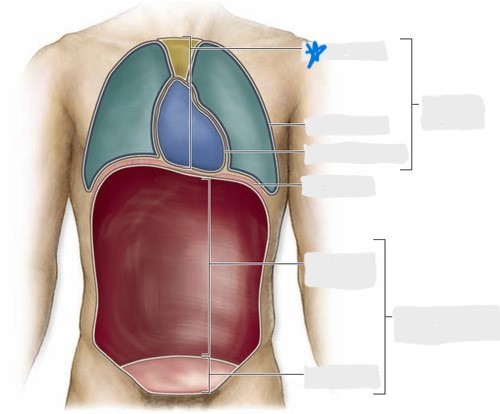

pleural cavity

pericardial cavity

mediastinum

abdominal cavity

pelvic cavity